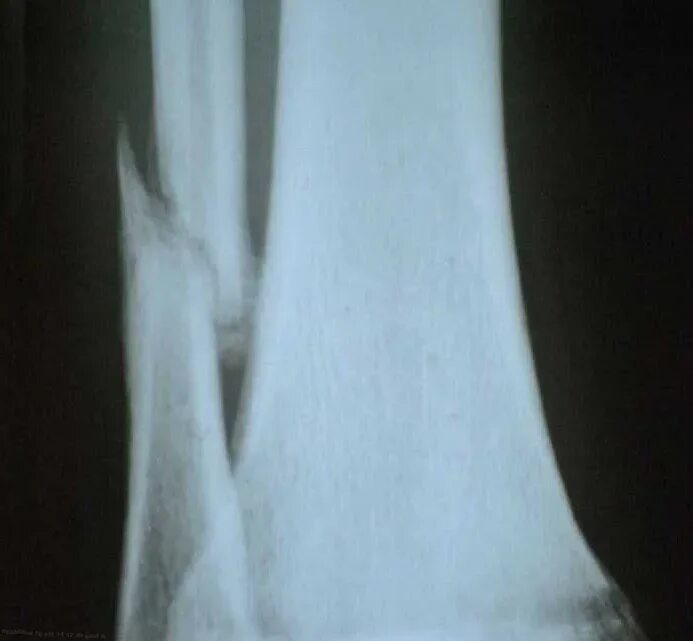

Сколько срастается малая берцовая кость